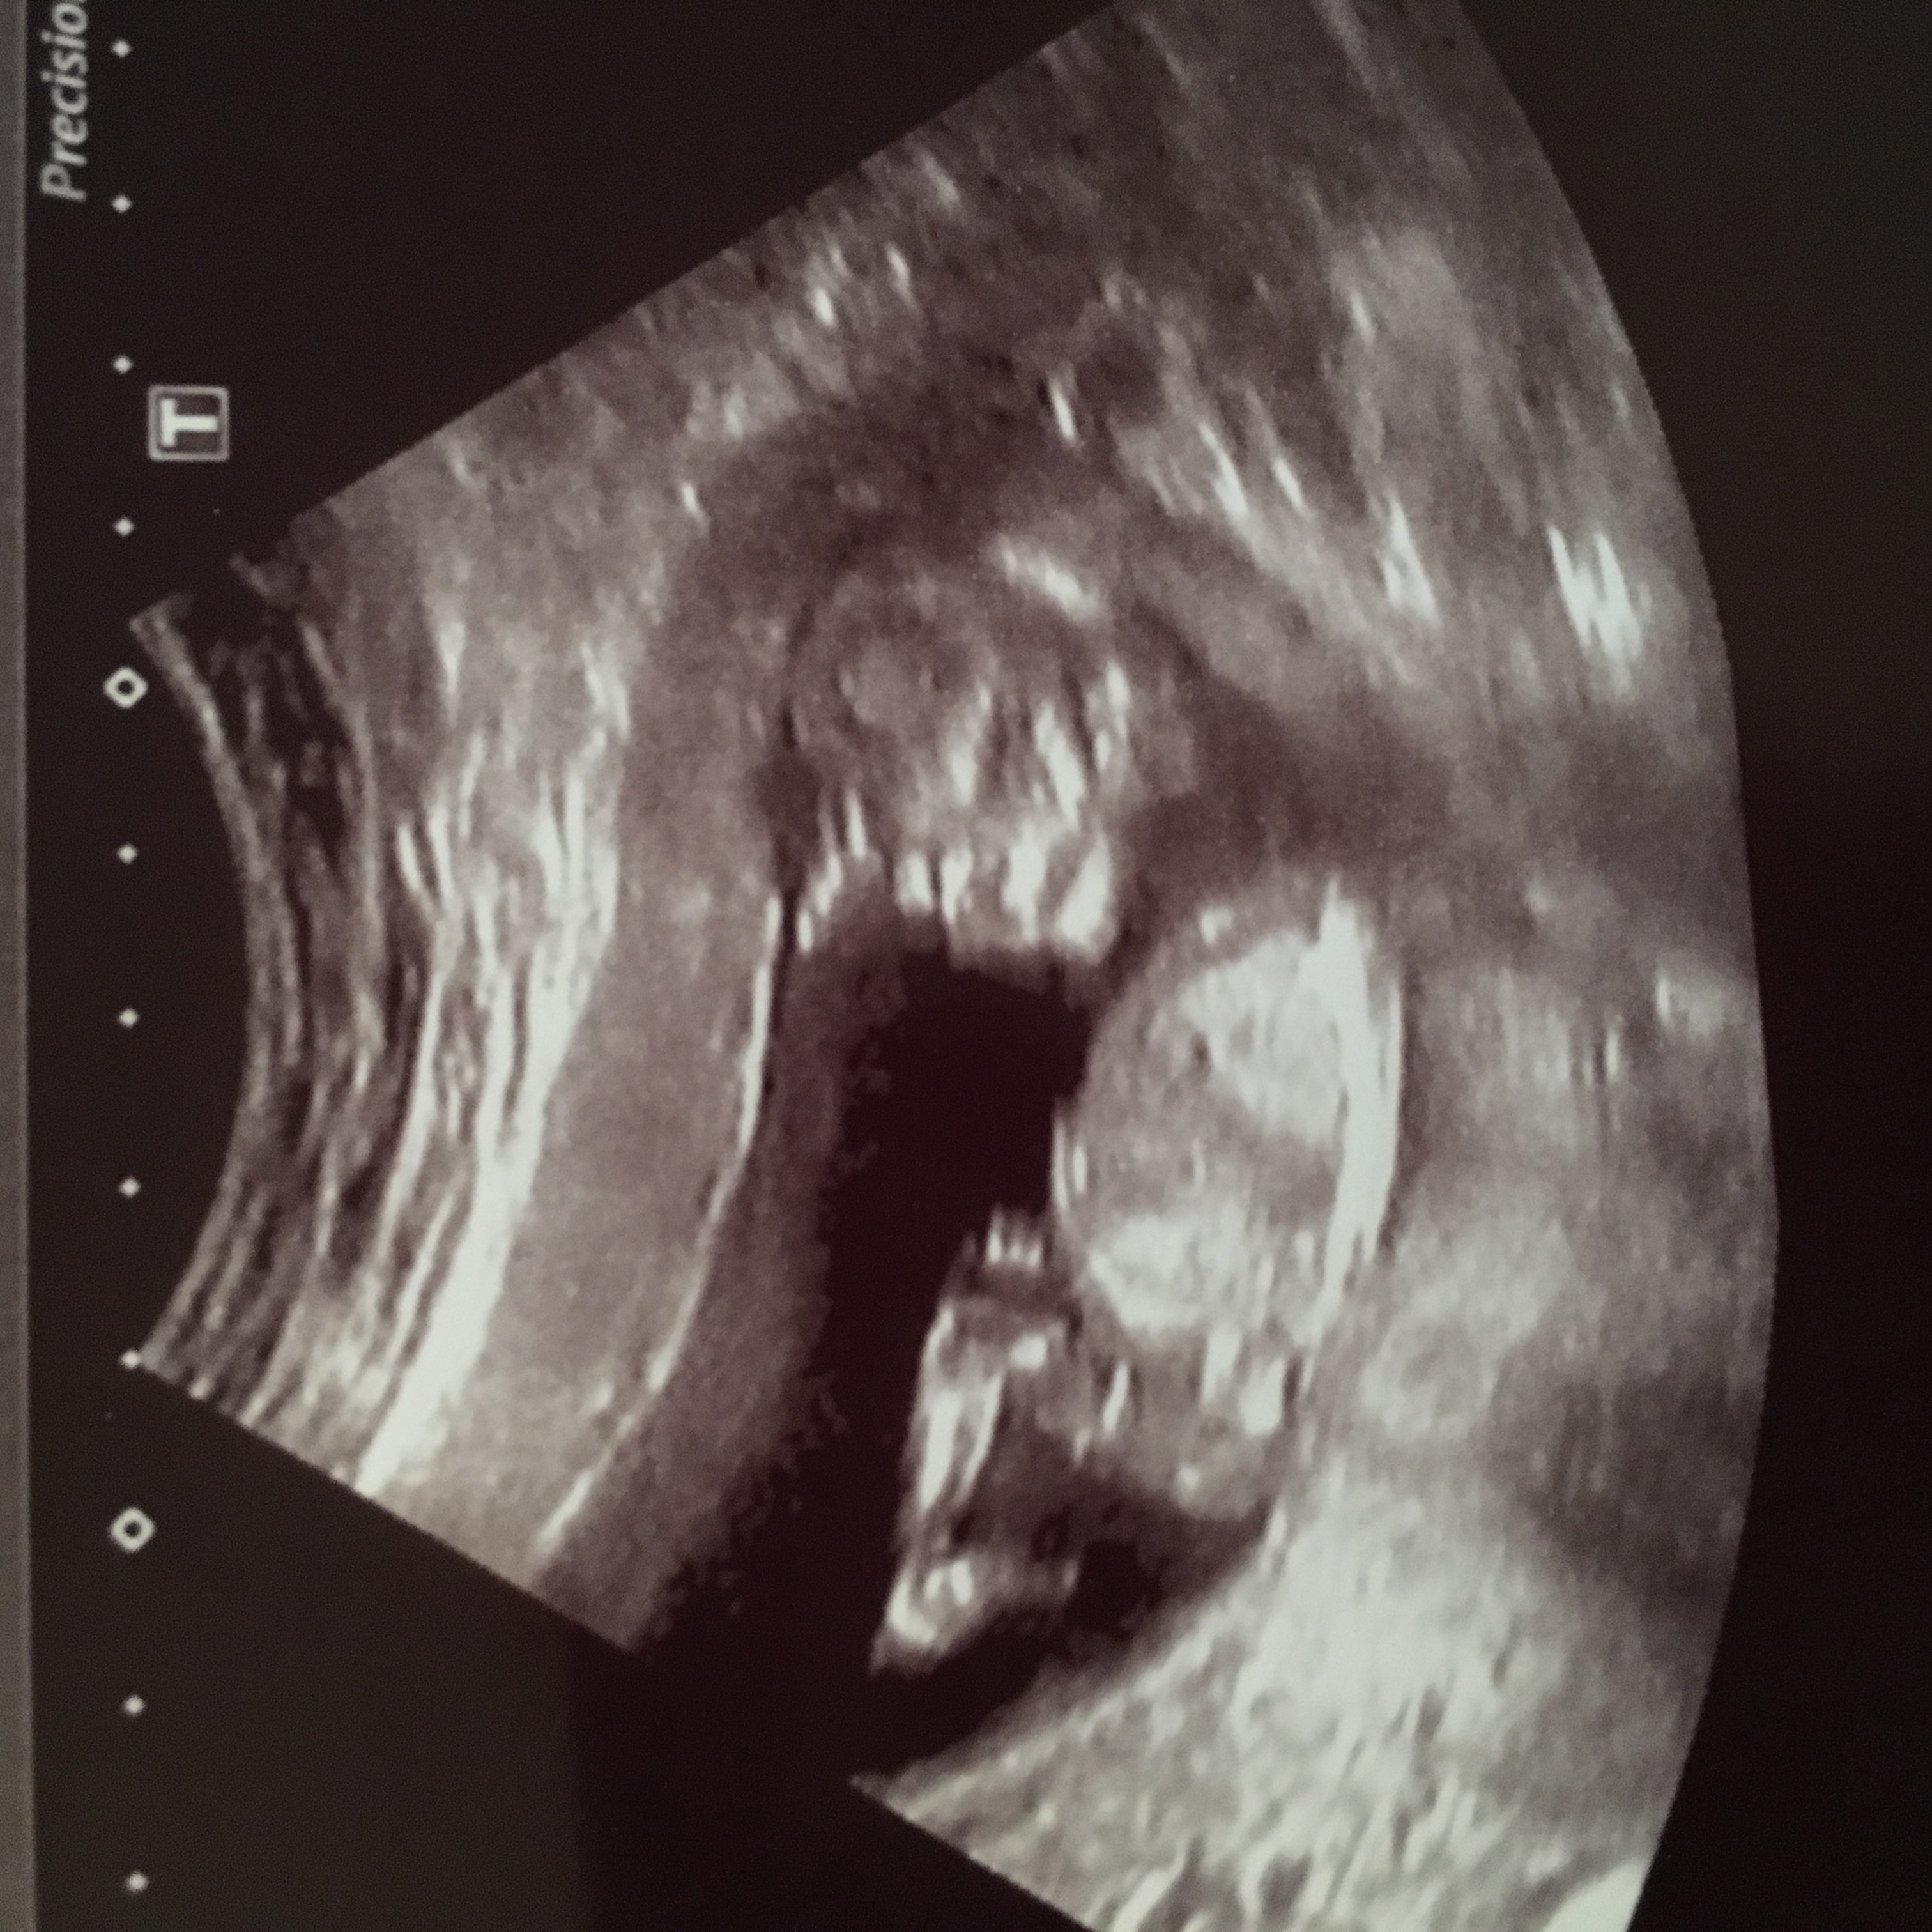

Attachment 27738Attachment 27740I understand there's no nub showing but I would love some predictions. Baby looks very different to my boy scans, but having said that I still look at it and think boy. Thank you!

Girly vibe from me. Def no cues just looks so dainty!lol

I also think it has a girlie vibe lol